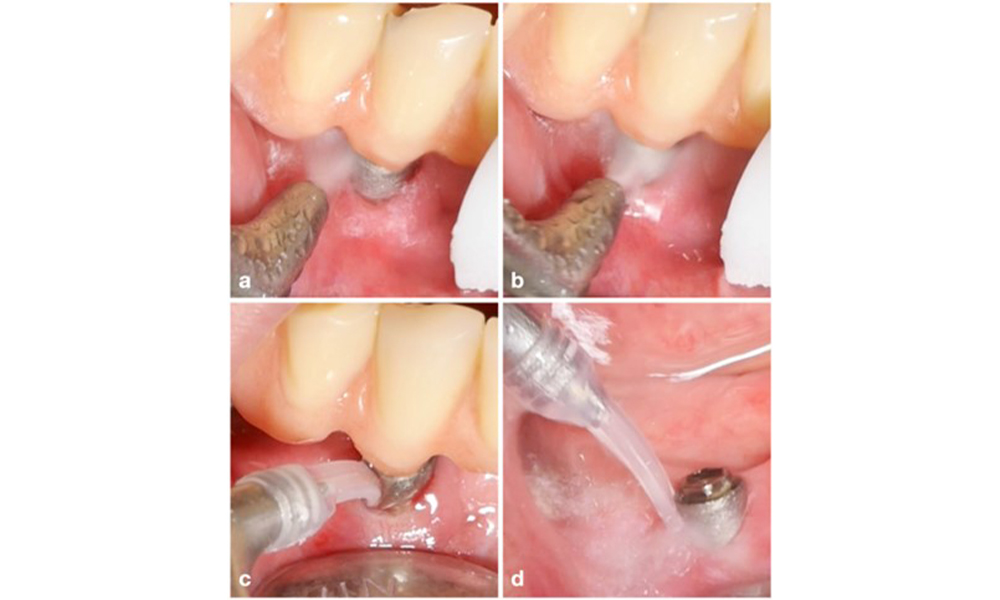

Die Wahl der Mittel hängt von den klinischen Gegebenheiten wie zum Beispiel Zahnstein im Unterschied zu weichen Belägen ab. Bei Zahnstein sollten als Erstes Titan- bzw. Kunststoffküretten oder Ultraschallscaler mit speziell geformter Spitze zum Einsatz kommen, gefolgt von einem Luftpoliergerät (Abb. 7). Bei ausschließlich weichen Belägen ist ein Luftpoliergerät allein unter Umständen ausreichend. Luftpoliergeräte sind bediener- und patientenfreundlich und mindestens so wirksam wie Standardinstrumente (Schwarz et al. 2015a).

Das Management einer Periimplantitis bei als therapierbar eingestuften Implantaten besteht aus einer nicht-chirurgischen Phase, oftmals gefolgt von einer chirurgischen Intervention. Bei den nicht-chirurgischen Verfahren kommen ähnliche Maßnahmen zum Einsatz wie bei der Behandlung einer periimplantären Mukositis. Laborexperimente lassen darauf schließen, dass Luftpoliergeräte mit subgingivaler Düse bei der Biofilmentfernung im Vergleich zu Hand- oder Ultraschallinstrumenten allem Anschein nach bestimmte Vorteile bieten (Herrera et al. 2023; Moharrami et al. 2019; Ronay et al. 2017) (Abb. 9).

Für Implantate mit modifizierten Oberflächen und intraossären Defekten mit deutlich höherem Potenzial einer Re-Osseointegration wird ein rekonstruktives Verfahren empfohlen (Monje et al. 2023; Renvert et al. 2009). Dabei können autogener Knochen, Knochenersatzmaterial und/oder Membranen zum Einsatz kommen (Abb. 13) (Donos et al. 2023). Selbstverständlich erfordert ein rekonstruktives Verfahren eine gründliche Dekontamination der Implantatoberfläche. Sowohl Labor- als auch präklinische Studien zeigen, dass eine vollständige Entfernung des Biofilms von der Implantatoberfläche nicht möglich ist (Subramani & Wismeijer 2012). Daher wird für eine wirksame Dekontamination eine Kombination mechanischer und chemischer Maßnahmen empfohlen, wobei jedoch keine bestimmte Methode als überlegen gelten kann (Ramanauskaite et al. 2023; Wilensky et al. 2023). Laut mehrerer Laborstudien zeigen Luftpoliergeräte bei der Entfernung von Biofilm eine überlegene Wirksamkeit (Francis et al. 2022; Keim et al. 2019, Sahrmann et al., 2015). Dabei ist jedoch unbedingt zu beachten, dass intraoperatives Luftpolieren als Off-Label-Use gilt.